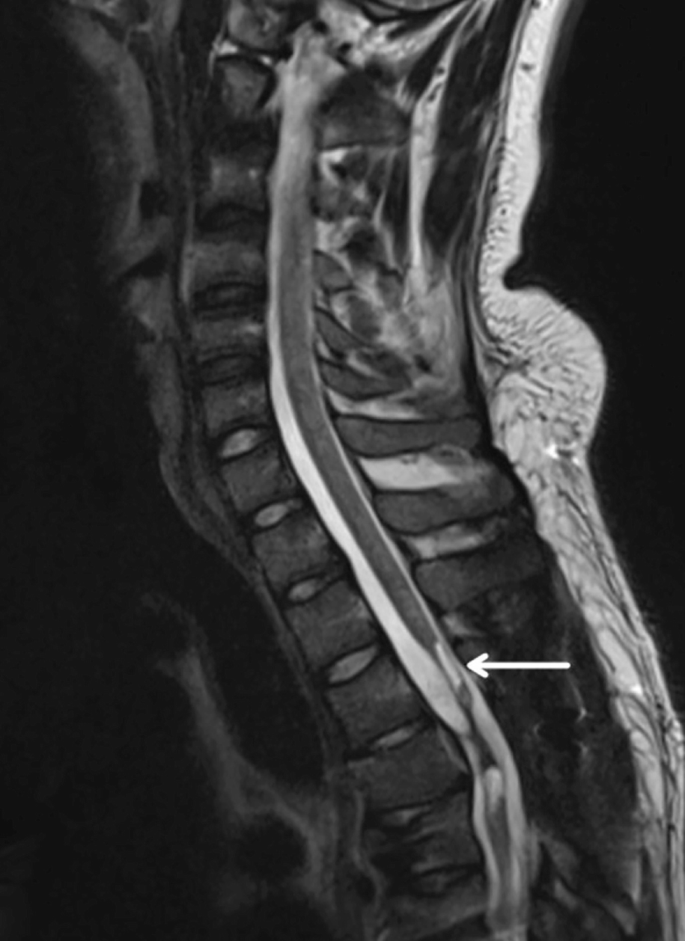

慢性期開始于損傷后約3-6個月,并持續患者的余生,典型特征是囊腫形成和嚴重的神經膠質瘢痕(圖2)。